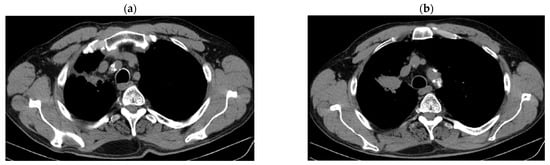

2. Case Presentation

2.3. Oncological Committee 07/25/2023 Recommended

- Consider rescue re-irradiation (SBRT), taking into account the current primary tumor dimensions of 24 × 34.2 mm on PET CT from 06/2023 and also the total dose previously administered (08–09/2020), the previously applied fractionation, the time between the two irradiations, the cellular repair time and the dose constraints for the organs at risk.

3. Case Results

| DOWNSTAGING from metastatic to locoregional stage | From cT3N3M1b(OSS) stage IVA | In cT2bN3M0, stage IIIB (without M1OSS) |